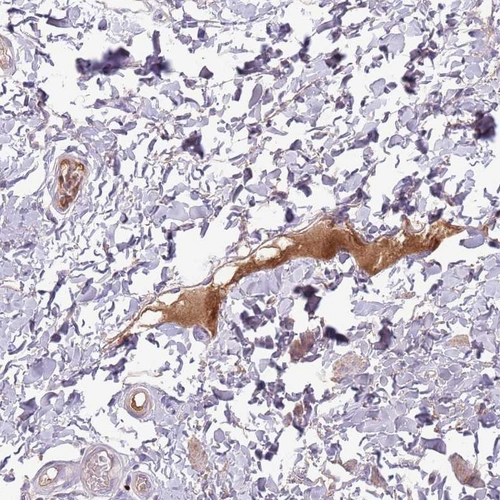

Immunohistochemical staining of human rectum shows strong positivity in plasma.